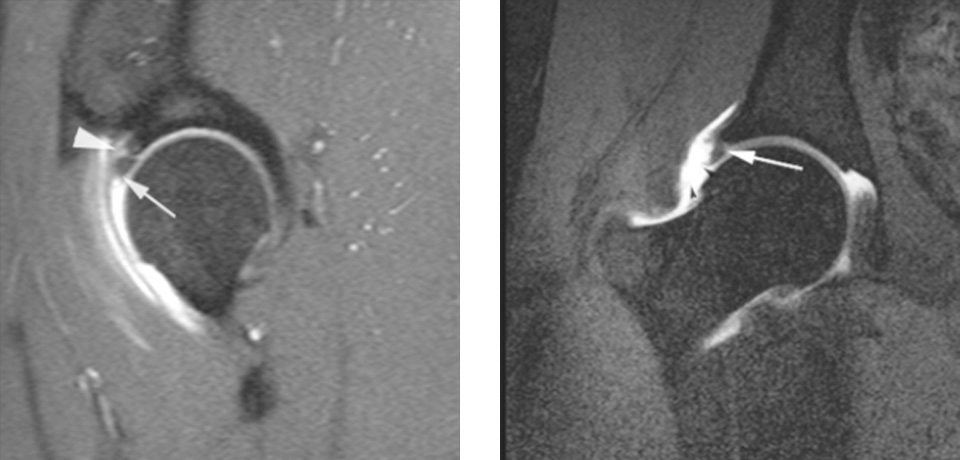

관절 조영 MRI 소견에서 고관절의 연골판 즉, 비구순이 파열된 것을 알 수 있다.

- 환자 동의하에 게시된 이미지입니다.